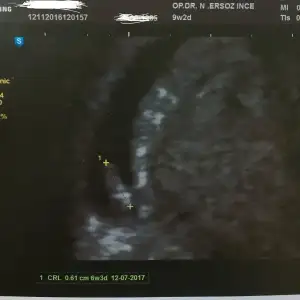

Kızlar bugün doktora gittik ve miniğimizi gördük sesini dinletmedi henüz ama minik kalp atışlarını gördük :) şuan herşey yolunda gibi.kese de yayvan fasulye gibi bişi ama normalmiş.doktorumuz çok iyi bu arada tavsiye ederim.güler yüzlü pozitif ve en önemlisi herşeyi sormadan açıklıyor.

Eklentiler

• IMG_3513.webp

IMG_3513.webp

10,7 KB · Görüntüleme: 88